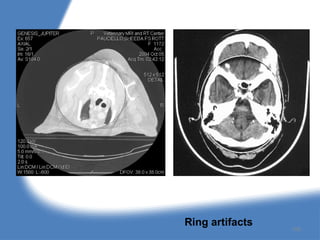

4. Ring artifacts :

157

Ring artifacts